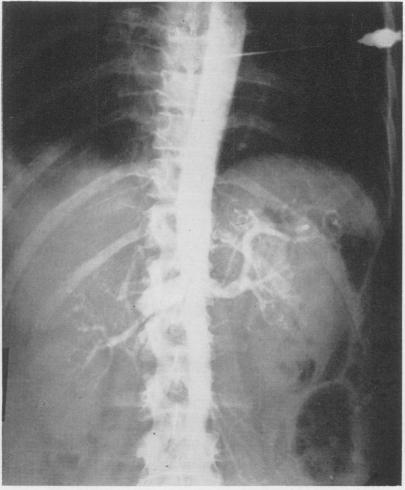

Treatment of aneurysm of the hepatic artery by excision; report of case.

Ann Surg. 1955 Jul;142(1):110-4. doi: 10.1097/00000658-195507000-00014.